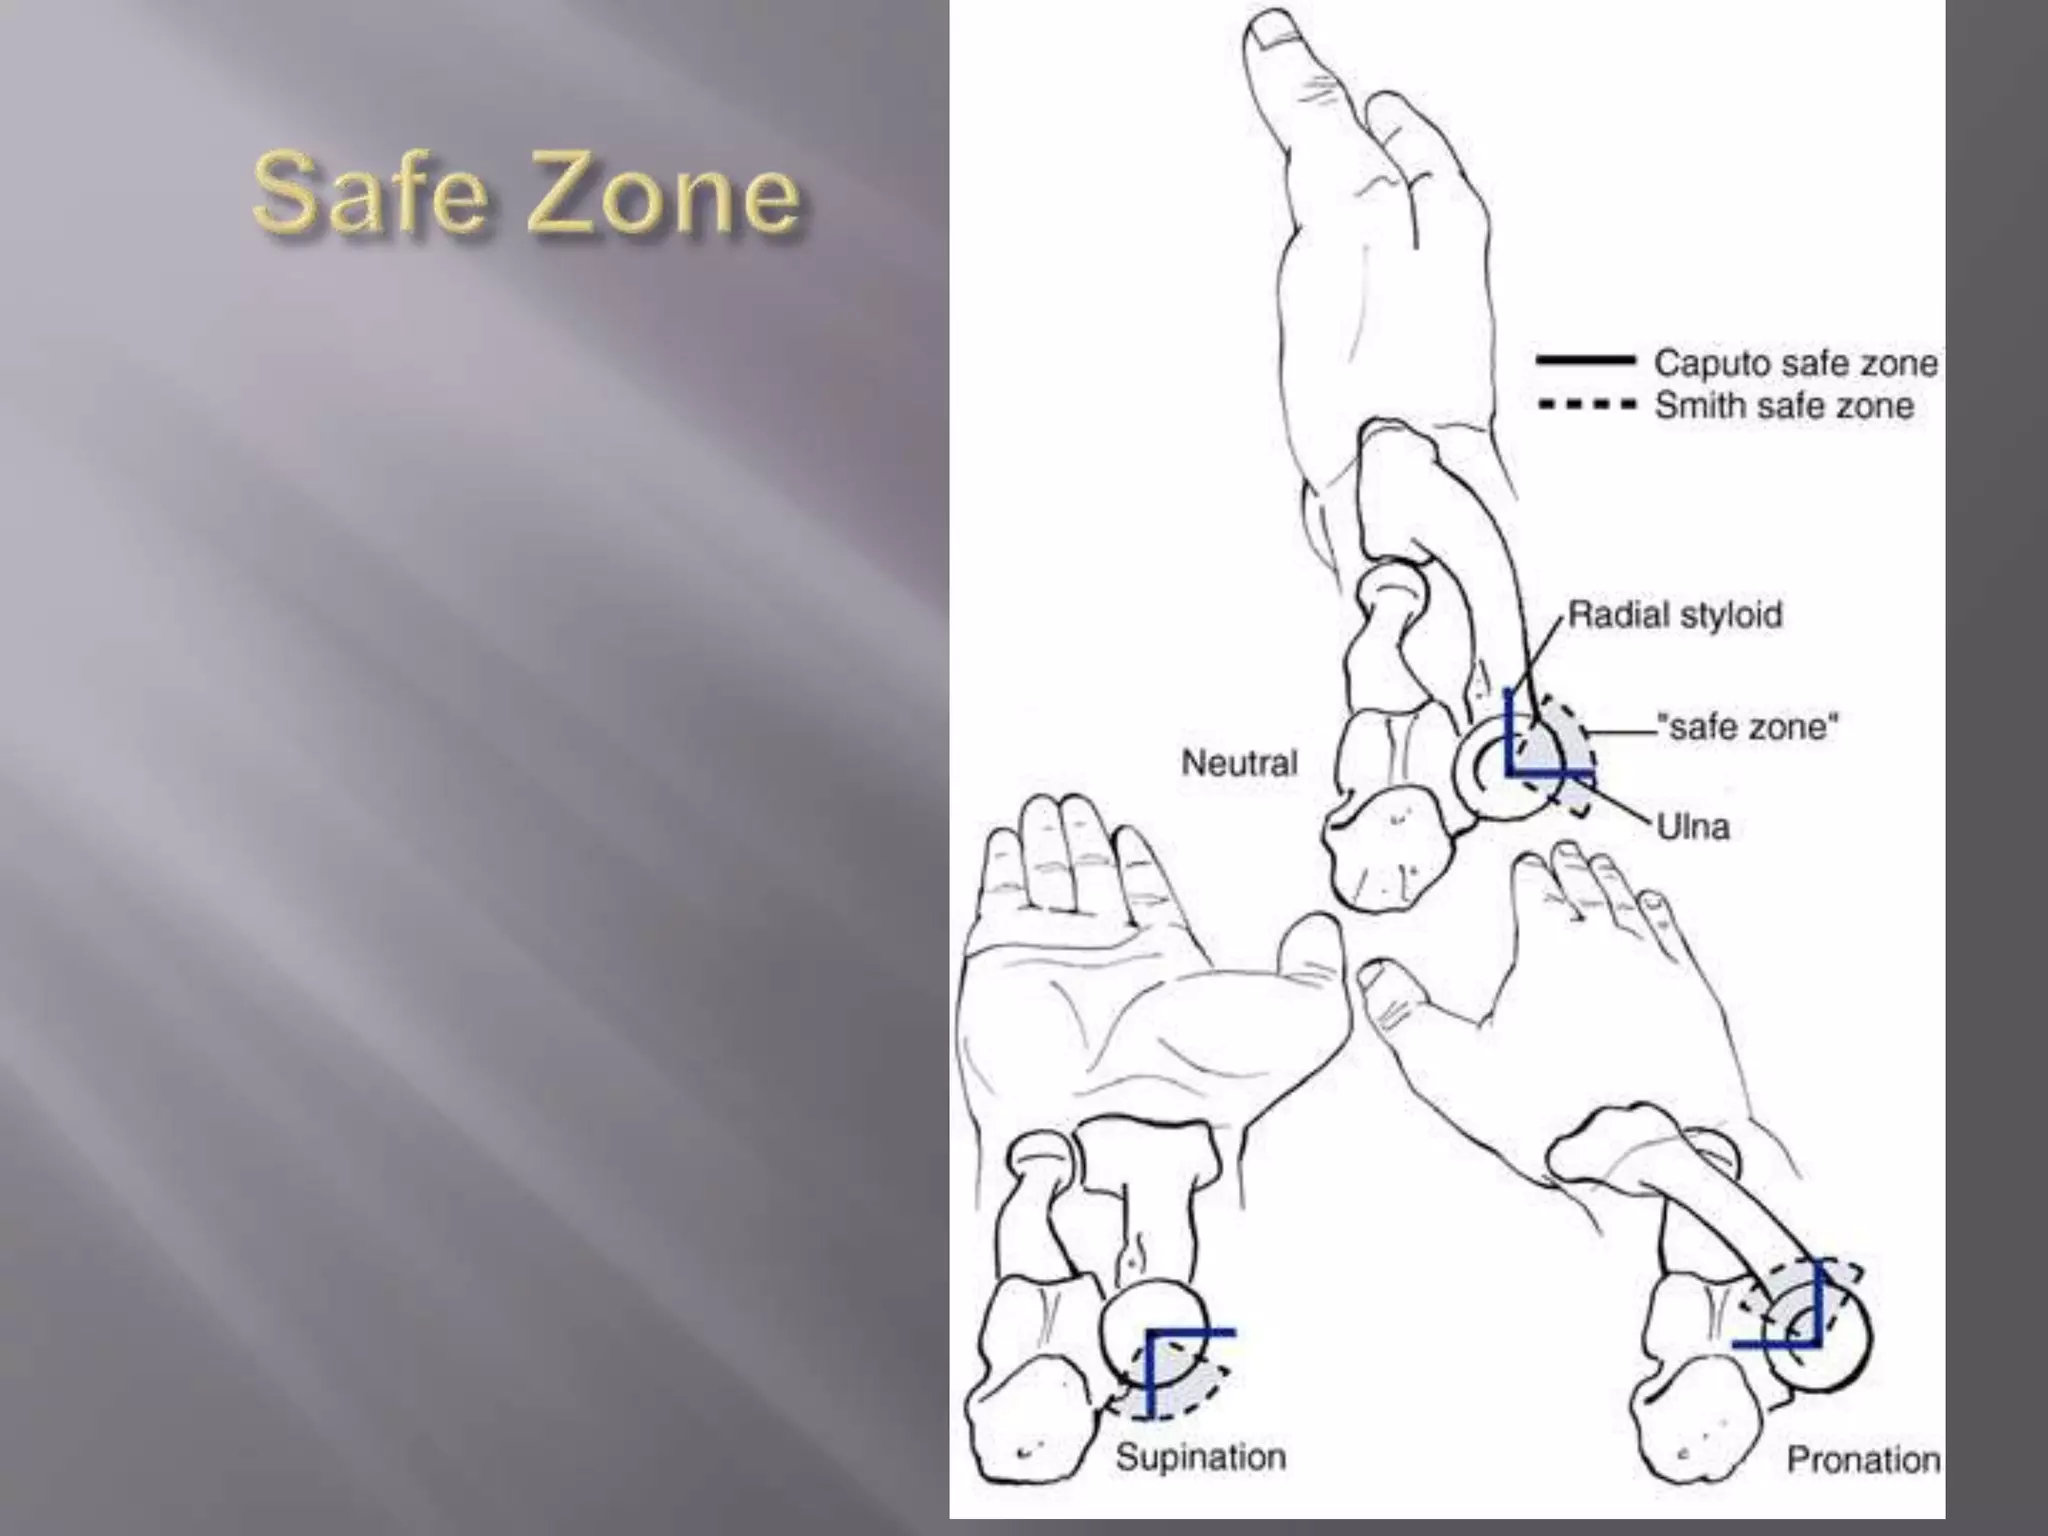

This document discusses the terrible triad injury of the elbow, which involves fractures of the radial head, coronoid process, and posterolateral dislocation. It notes the poor outcomes associated with this injury like stiffness, instability, and hardware failure. The document outlines the relevant anatomy of the medial collateral ligament and lateral uncular collateral ligament. It describes the mechanism of injury, known as the fall on an outstretched hand, and how the ligaments and capsule fail in this injury. Diagnostic imaging and classification of radial head and coronoid fractures are covered. Treatment options including observation, resection, open reduction internal fixation, and replacement are presented. Surgical approaches and techniques are also outlined.